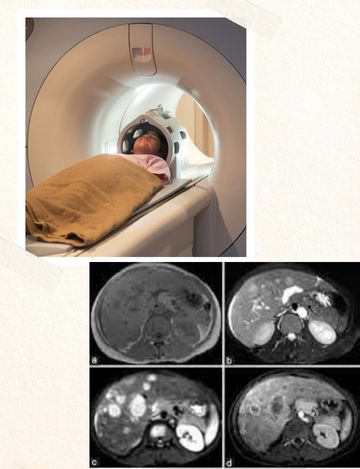

MRI Scan for Triphasic liver in Hyderabad

MRI Scan for Triphasic liver is a detailed scan of the liver and its blood supply. The liver is our body’s main detoxification center and the most resilient. However, the liver can get damaged in varying degrees due to infections, injuries, chronic alcoholism, and even hereditary diseases like Wilson’s disease and hemochromatosis. Liver damage usually manifests as jaundice, nausea, pain in the upper right abdomen, vomiting, indigestion, and severe cases, even bleeding manifestations. To rule out any lesions and to make out the blood supply to the liver, a radiologist can do an MRI triphasic liver scan.

The MRI triphasic liver scan is not at all a painful process. It only involves one dye injection and serial photographs of the liver at different periods. One time frame will show an MRI of the liver, one will give a picture of the liver arterial supply, and one will show a picture of the venous drainage.

An MRI triphasic liver may take 90 mins or more as contrast is used. During this period, multiple pictures of the desired part are taken from different angles and techniques.